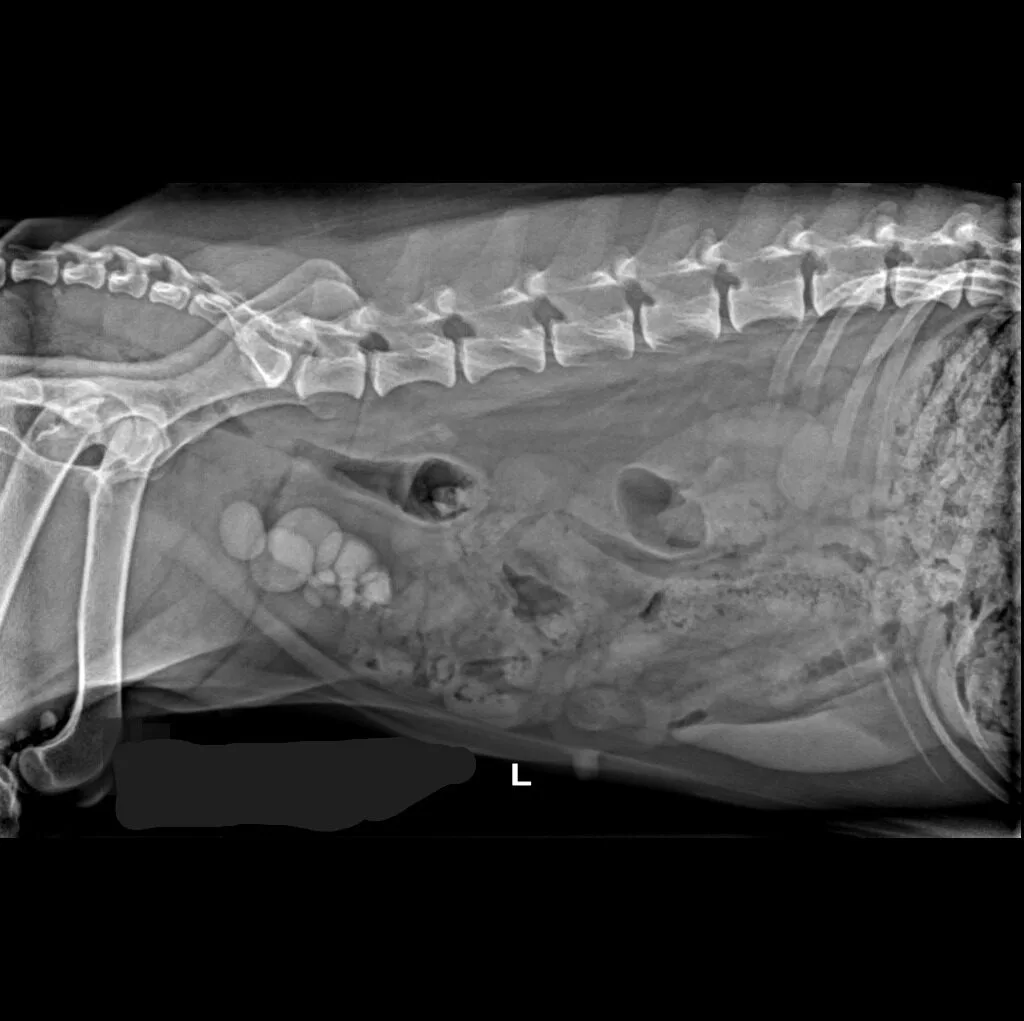

At Grand Ave. Pet Hospital, we utilize digital radiography to diagnose and monitor a wide range of medical conditions in pets. Digital X-rays provide clearer images, faster results, and safer radiation levels, ensuring the best possible care for your furry companion.

🔹 Abdominal & Gastrointestinal Issues – Detecting obstructions, tumors, or organ abnormalities